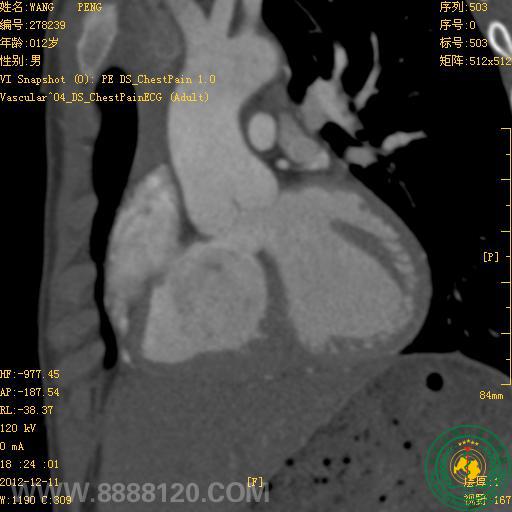

我院新双源CT在先天性心脏病中的首例应用

宜宾市第二人民医院 图文